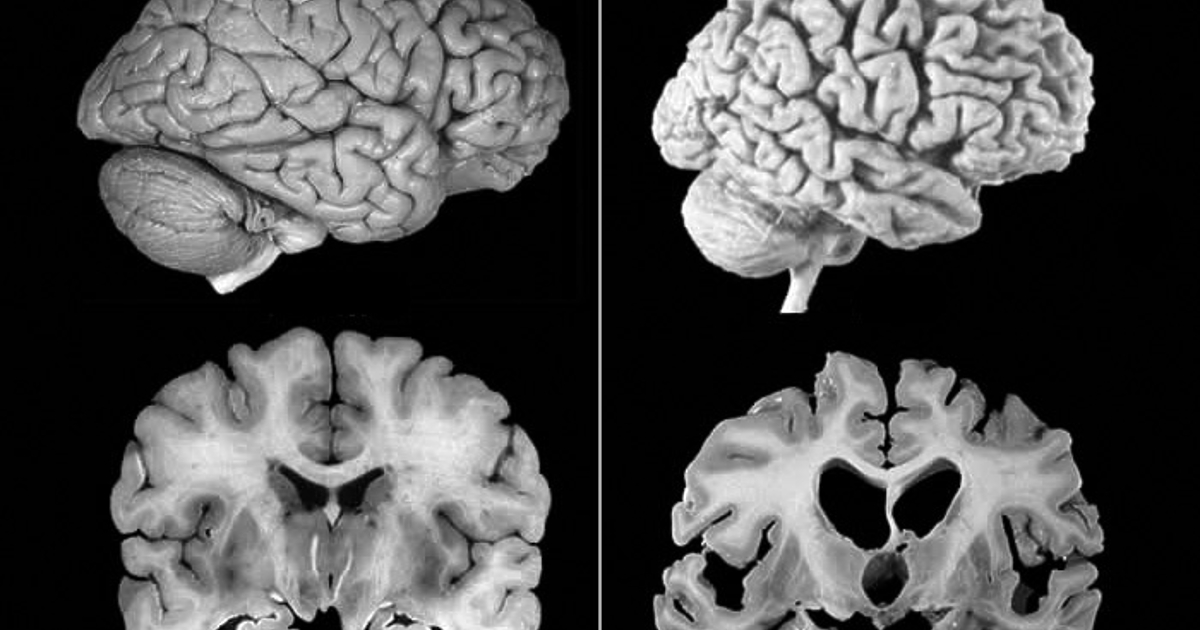

Отдавна е известно, че прионовите болести могат да се предават - да вземем за пример посредством консумация на инфектирано с приони говеждо месо. От там идва и нехрофесионалното наименование „ Луда крава “. Въпреки това, по време на проучванията на смъртни случаи от CJD, при които засегнатите са били лекувани с хормон на растежа, лекарите откриват и ясно изразени отлагания на погрешно сгънатия протеин амилоид бета (Aß) в мозъците на някои от умрелите. Тези отлагания са патологична характерност на заболяването на Алцхаймер и евентуално са и нейната съществена причина.